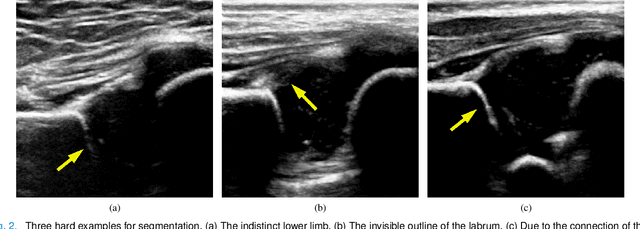

Abstract:The ultrasound (US) screening of the infant hip is vital for the early diagnosis of developmental dysplasia of the hip (DDH). The US diagnosis of DDH refers to measuring alpha and beta angles that quantify hip joint development. These two angles are calculated from key anatomical landmarks and structures of the hip. However, this measurement process is not trivial for sonographers and usually requires a thorough understanding of complex anatomical structures. In this study, we propose a multi-task framework to learn the relationships among landmarks and structures jointly and automatically evaluate DDH. Our multi-task networks are equipped with three novel modules. Firstly, we adopt Mask R-CNN as the basic framework to detect and segment key anatomical structures and add one landmark detection branch to form a new multi-task framework. Secondly, we propose a novel shape similarity loss to refine the incomplete anatomical structure prediction robustly and accurately. Thirdly, we further incorporate the landmark-structure consistent prior to ensure the consistency of the bony rim estimated from the segmented structure and the detected landmark. In our experiments, 1,231 US images of the infant hip from 632 patients are collected, of which 247 images from 126 patients are tested. The average errors in alpha and beta angles are 2.221 degrees and 2.899 degrees. About 93% and 85% estimates of alpha and beta angles have errors less than 5 degrees, respectively. Experimental results demonstrate that the proposed method can accurately and robustly realize the automatic evaluation of DDH, showing great potential for clinical application.